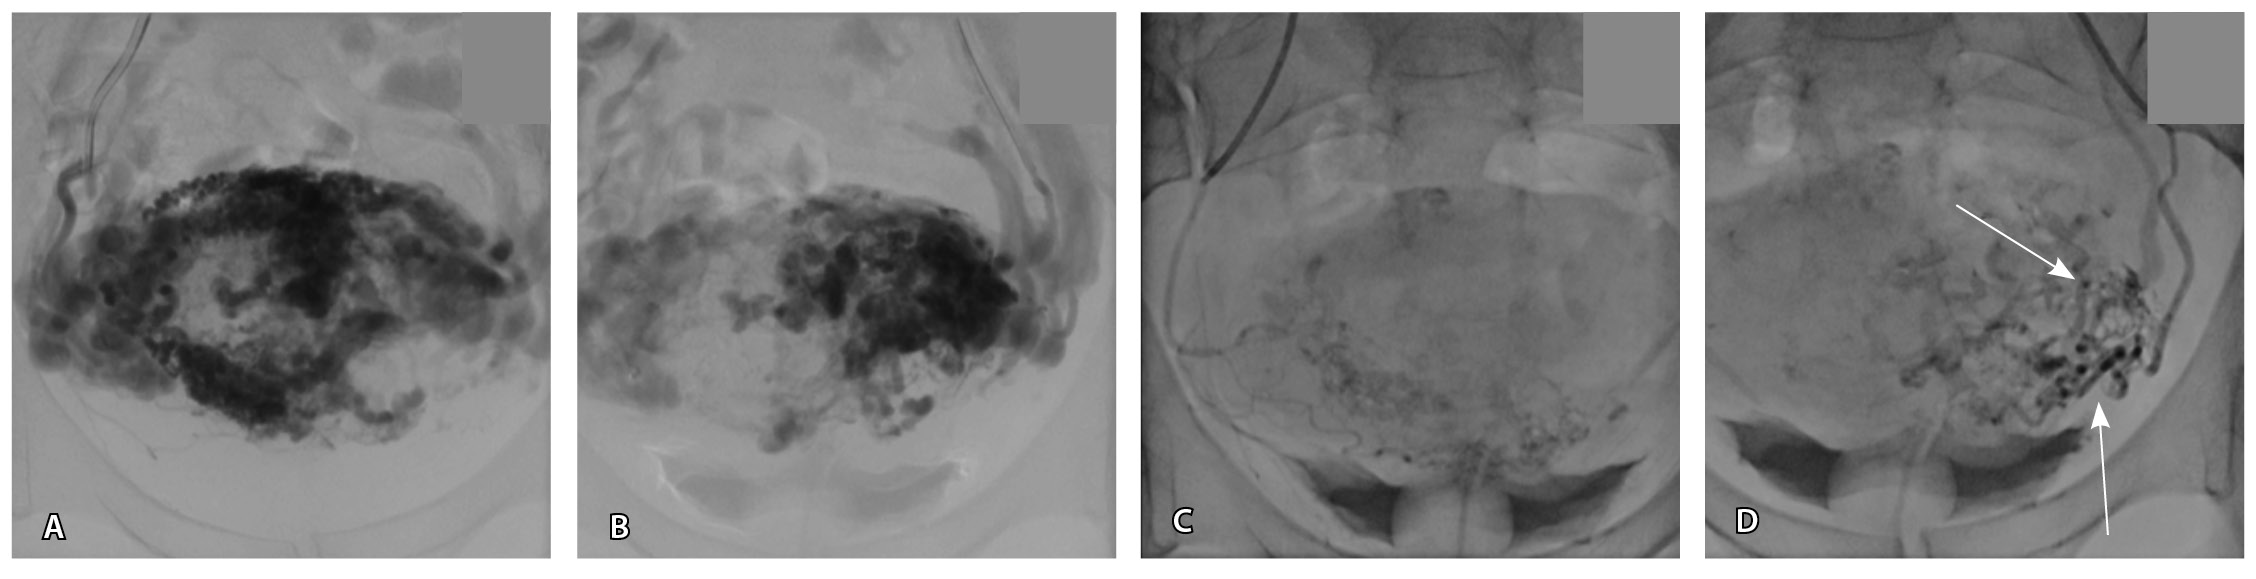

Исходя из клинической и визуальной картины, пациентке выполнено оперативное лечение. Первым этапом проведена эмболизация маточных артерий. Под местной анестезией раствором ропивакаина пунктирована правая лучевая артерия. Установлен интродьюсер 5F. Катетером НН последовательно катетеризированы левая и правая внутренние подвздошные артерии, выполнена ангиография. На ангиограммах: артериовенозная мальформация в проекции матки; афферентные артерии – маточные и цервиковагинальные – с обеих сторон, две ветви 1 мм в диаметре от левой внутренней подвздошной артерии; эфферентные сосуды – вены параметрия, внутренние подвздошные вены и яичниковые вены с обеих сторон (рис. 4).

Рис. 4. Данные рентгеноконтрастной ангиографии. А, Б – ангиограммы бассейнов правой и левой маточных артерий. Зоны патологической васкуляризации в проекции тела матки: массивная сеть измененных артерий и вен, ранний артериовенозный сброс в вены параметрия, внутренние подвздошные вены и яичниковые вены с обеих сторон. В, Г – ангиограммы бассейнов правой и левой цервиковагинальных артерий. Контрастирование зоны патологической васкуляризации в проекции шейки и нижнего отдела тела матки, ранний артериовенозный сброс в вены параметрия преимущественно слева и в левую внутреннюю подвздошную вену (стрелки)